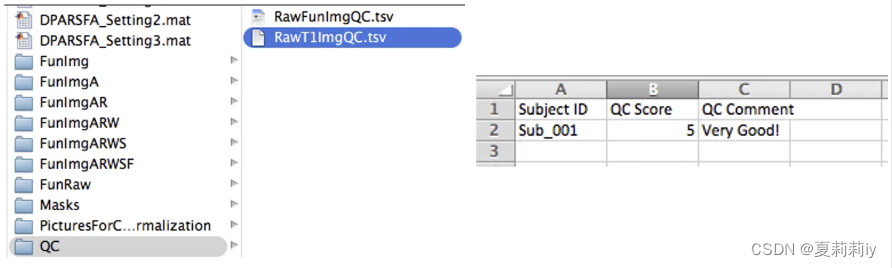

(1)dpabi→Quality Control(⭐这些应该是进行了数据处理之后才有的文件,不是原始数据集)

(2)QC:Raw T1

①打开的要是如下.tsv文件,可以修改tsv文件中的数值